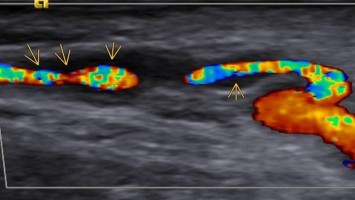

Was das Auge bei Long-COVID-Patienten verrät

Bildnachweise